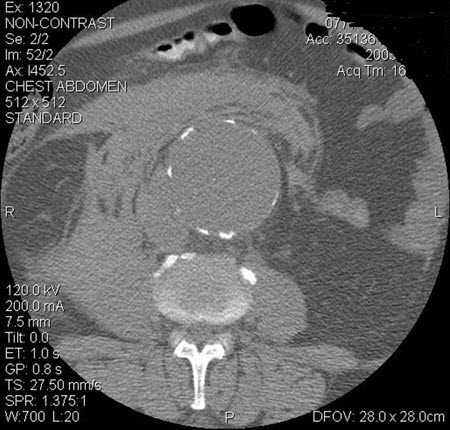

Abdominal aortic aneurysm

Abdominal aortic aneurysm: CT scan of a ruptured AAA

University of Michigan, specifically the cases of Dr Upchurch reflecting the Departments of Vascular Surgery and Radiology